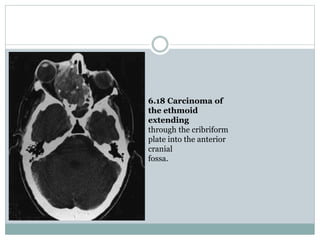

Paranasal sinus tumours

Tumours of the paranasal sinuses may spread directly

to involve the brain. These uncommon tumours

most frequently arise from the ethmoid or

maxillary sinuses, less frequently from the sphenoid

sinus and rarely from the frontal sinus. The

tumours invade through the floor of the anterior

cranial fossa in the region of the cribriform plate

and may extend through the dura into the frontal

lobe (Fig. 6.18). The tumours are usually squamous

cell carcinoma and less frequently adenocarcinoma

or adenoid cystic adenocarcinoma.

6.18 Carcinoma of

the ethmoid

extending

through the cribriform

plate into the anterior

cranial

fossa.